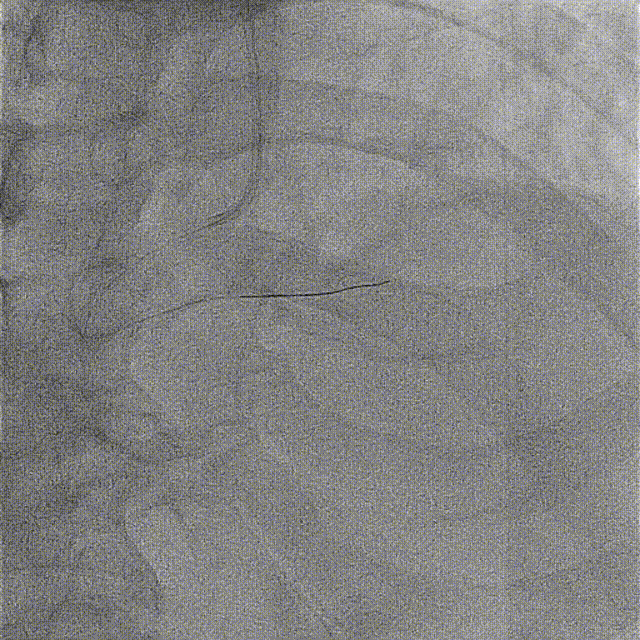

先后于3条分支球囊低压扩张,及冠脉内注入欣维宁。

再次沿PD导丝抽吸,注射器无明显回血,缓慢回拉退出抽吸导管,冲洗后未见明显血栓;但指引导管压力消失,心电正常。考虑血栓嵌顿于指引导管,尝试以注射器连接指引导管反复回抽后回血顺畅,抽出约3cm粗大血栓。